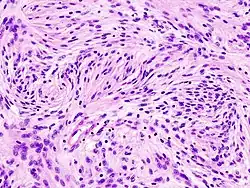

Meningiomas

Os meningiomas são os tumores cerebrais extrínsecos ou extra-axiais intracranianos mais comuns que surgem das células da aracnóide, a membrana que reveste o cérebro e a medula espinhal. A incidência desta neoplasia é de cerca de 2 casos por ano por 100.000 Residente. São mais comuns em mulheres na sexta e sétima décadas. Sua frequência é maior em pacientes com neurofibromatose tipo 2. A perda do cromossomo 22 é característico de meningiomas, embora o significado prognóstico desse achado ainda não esteja claro.

Os pacientes com meningioma podem apresentar sintomas típicos de uma lesão craniana maciça, incluindo convulsões e déficits neurológicos focais. Como o meningioma também pode ser assintomático, às vezes eles são detectados na tomografia computadorizada e na ressonância magnética por outros motivos. Este tumor de ressonância tem uma aparência característica, geralmente consistindo em realce uniforme de contraste ao longo da dura-máter com separação clara do parênquima cerebral. Outra característica, embora não presente em todos os casos, é a chamada "cauda dural", representada por uma protuberância que se estende além da lesão e indica o ponto de ancoragem na dura-máter.